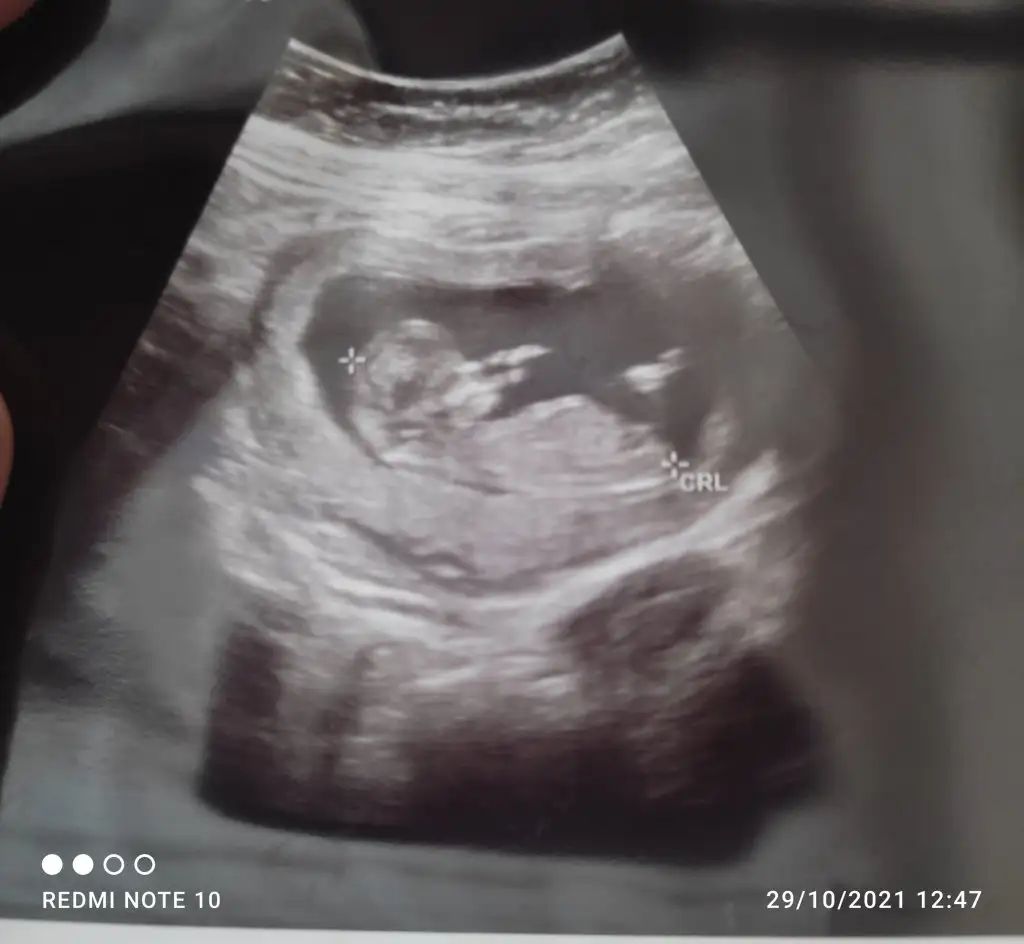

Kız gibi geldi bana.